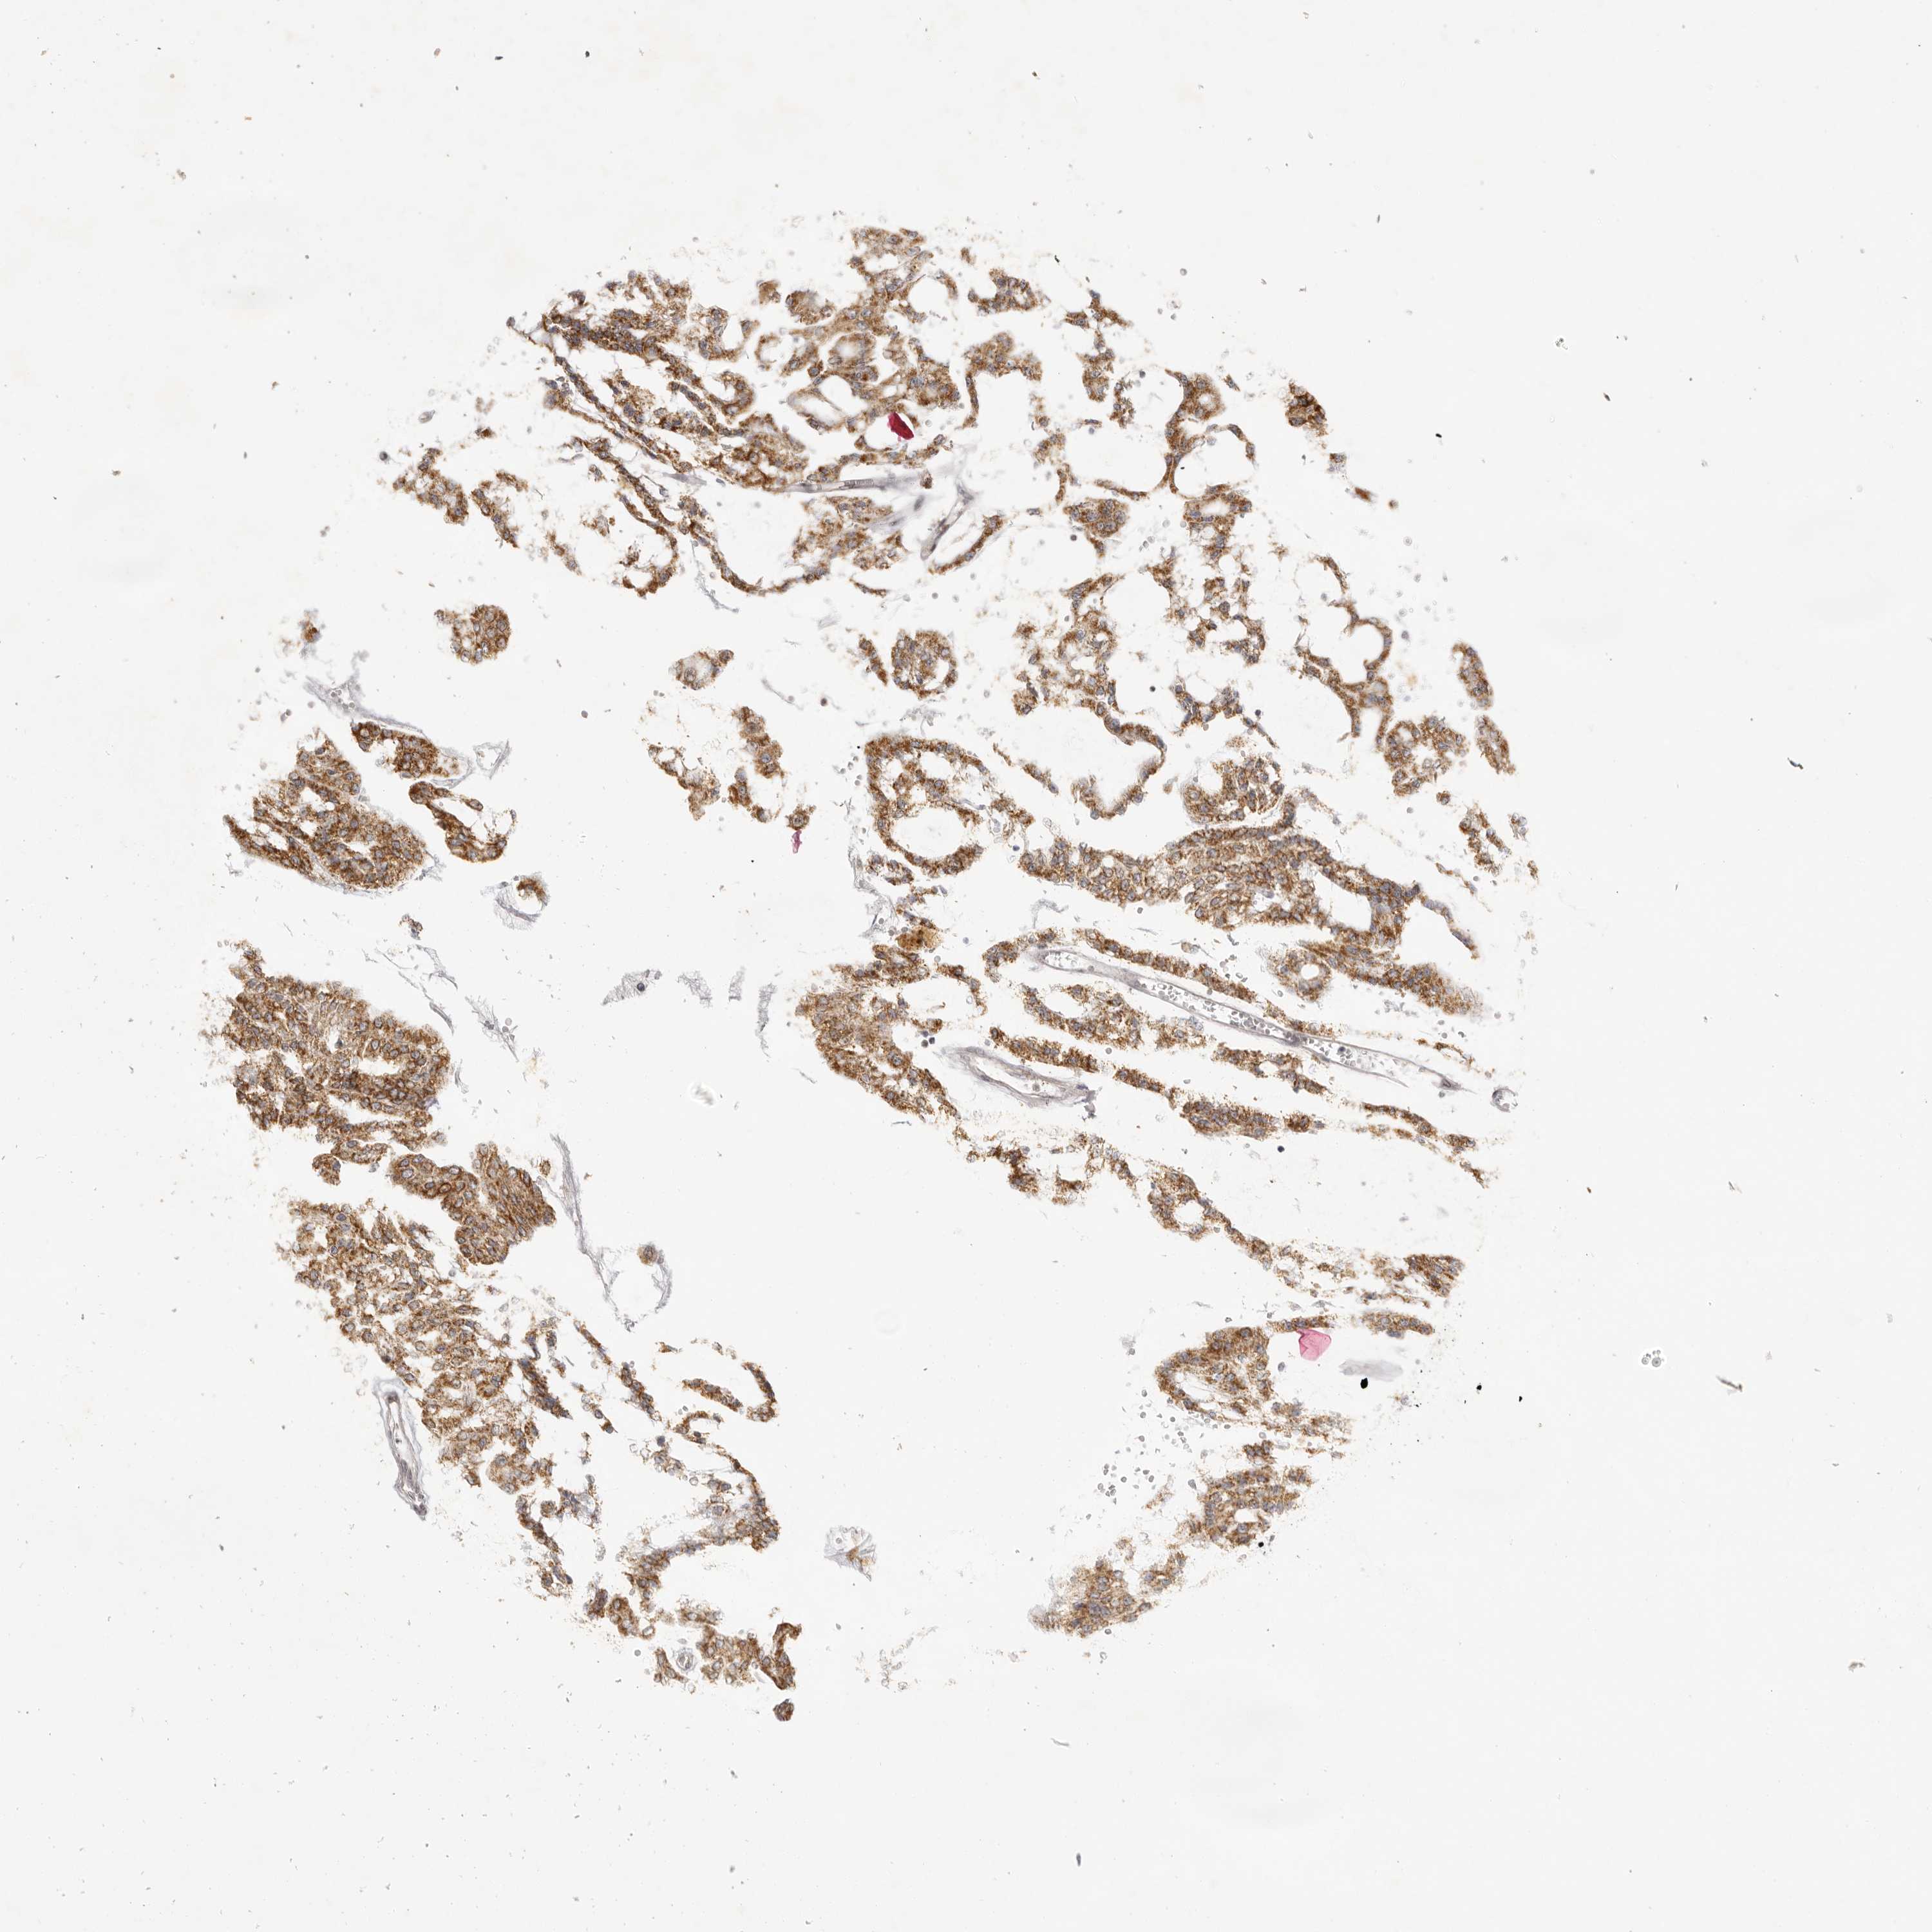

CANCER RENAL CANCER Show tissue menu

KICH TCGA KIRC TCGA KIRC VALIDATION KIRP TCGA PROTEIN RCC CPTAC PROTEIN EXPRESSION